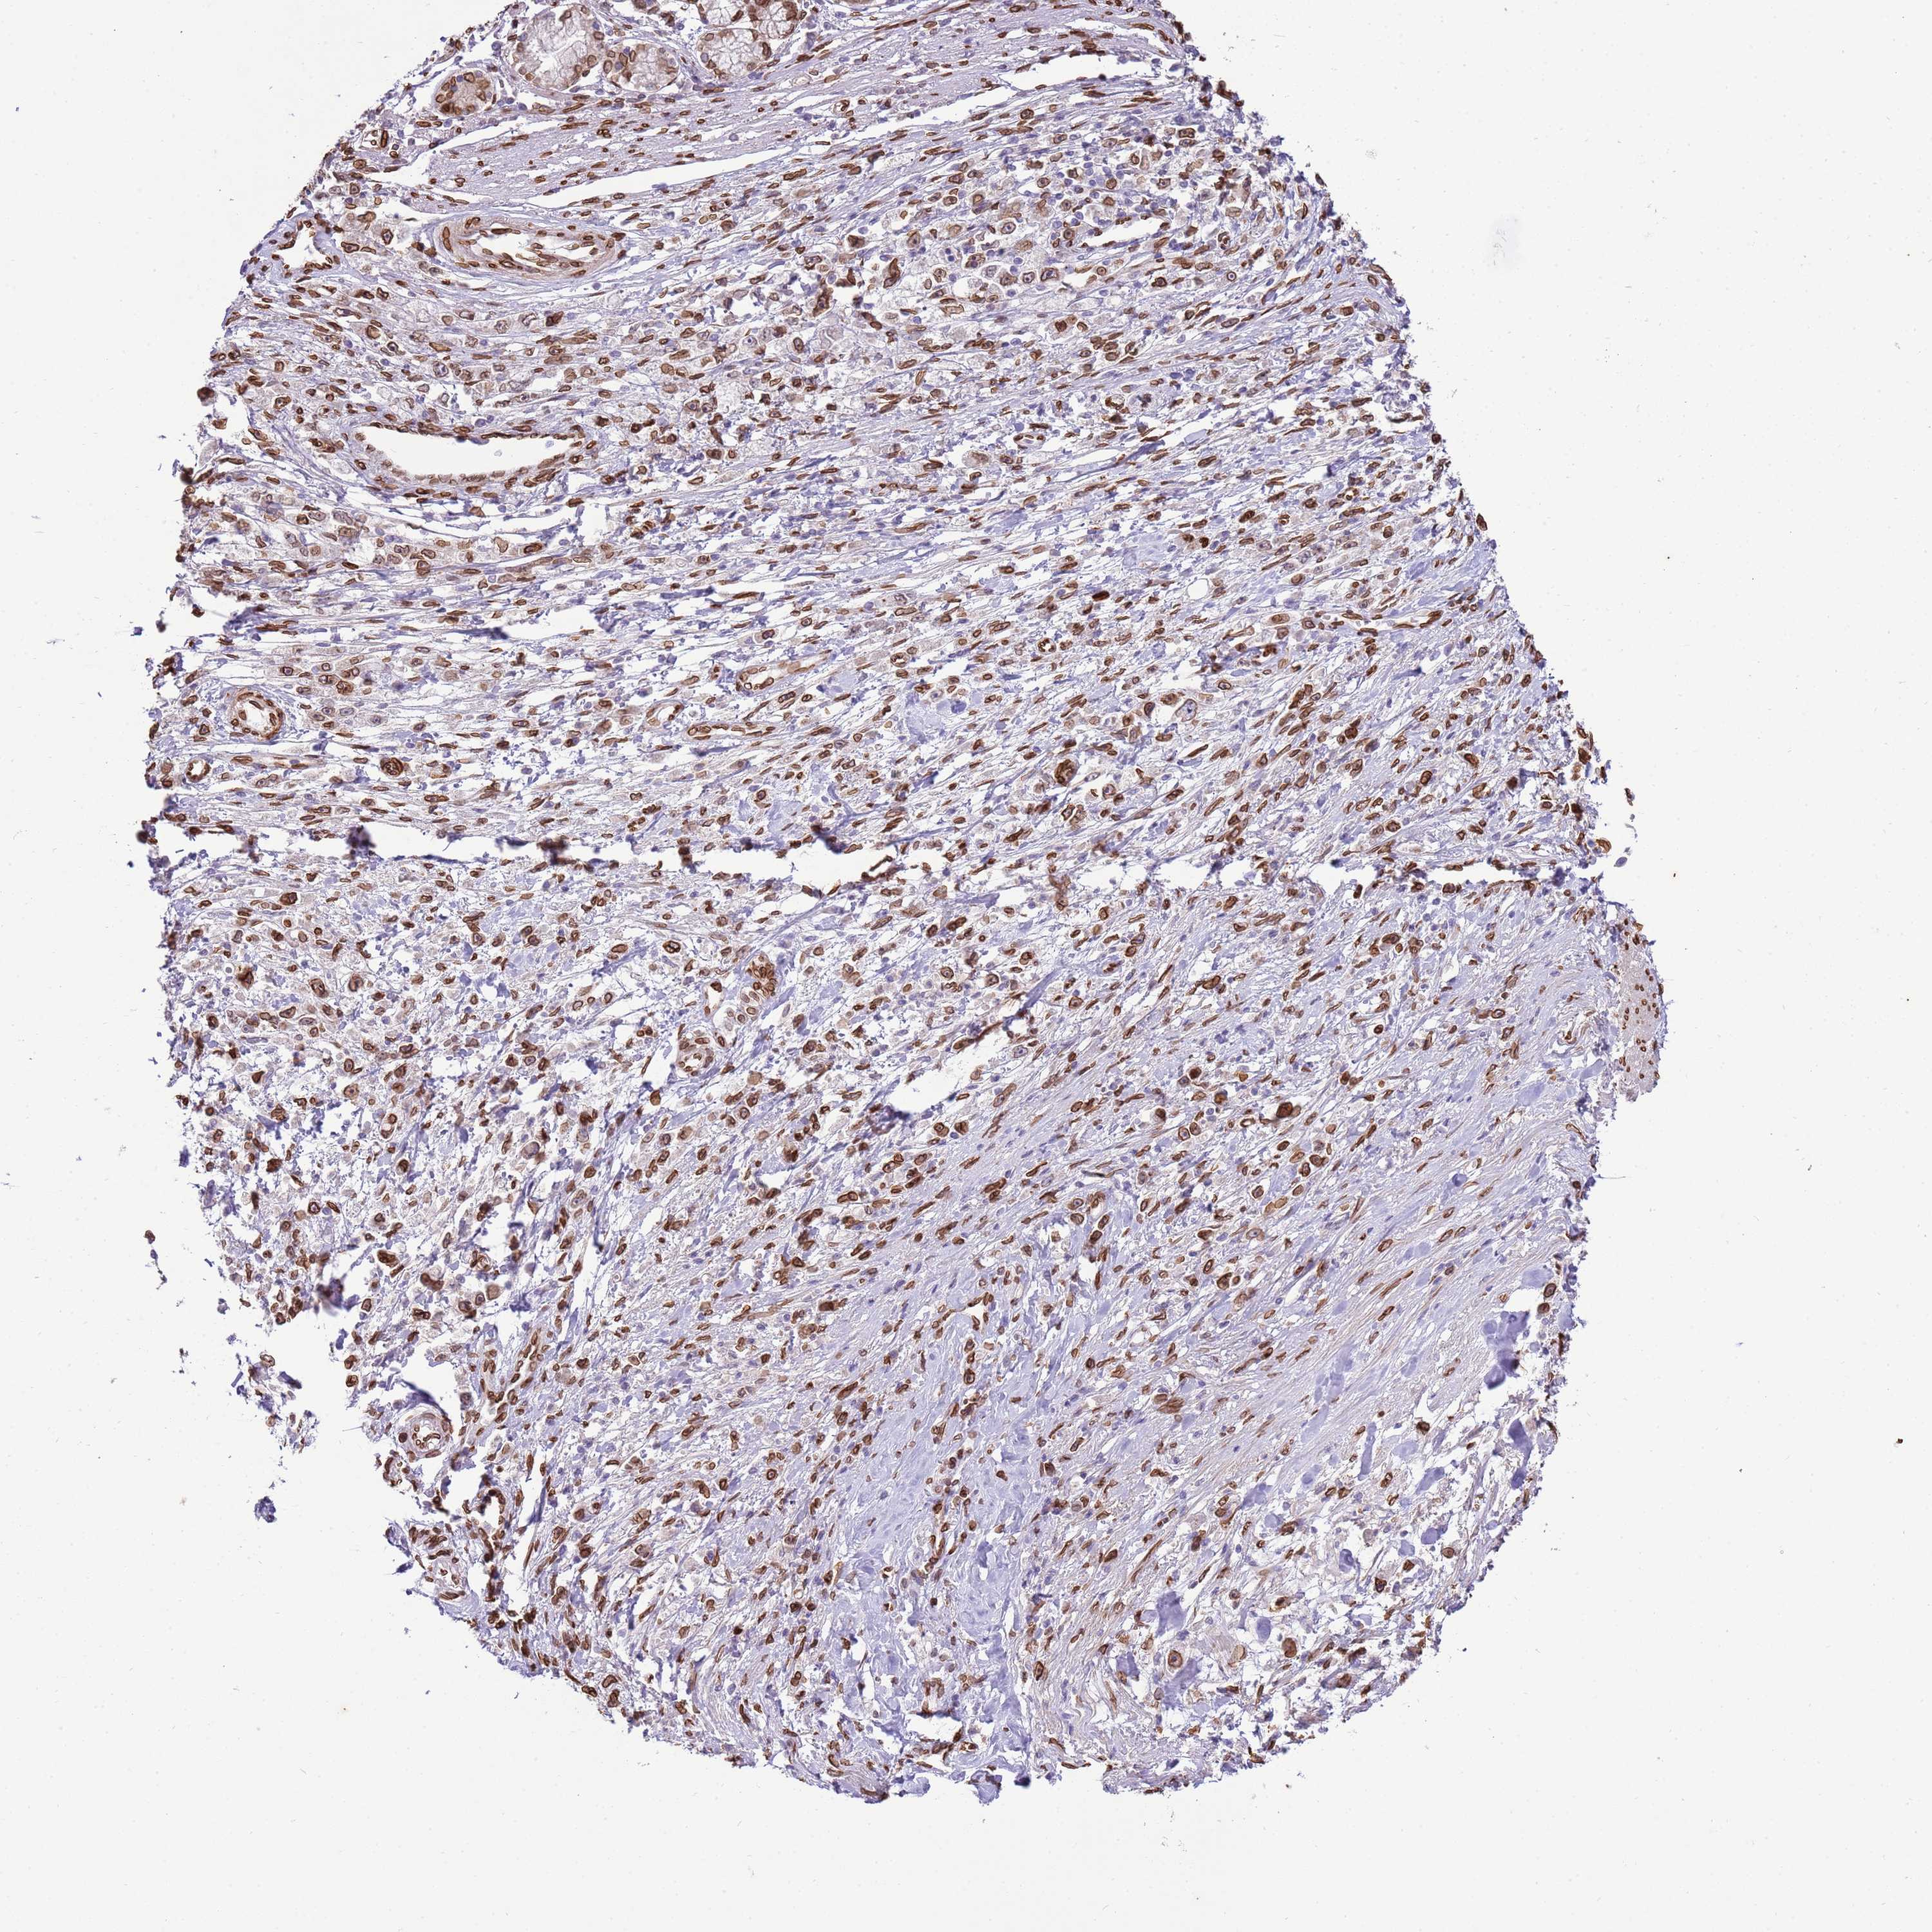

STOMACH CANCER - Protein expressioni

A mouse-over function shows sample information and annotation data. Click on an image to view it in a full screen mode. Samples can be filtered based on level of antibody staining by selecting one or several of the following categories: high, medium, low and not detected. The assay and annotation is described here.

Note that samples used for immunohistochemistry by the Human Protein Atlas do not correspond to samples in the TCGA dataset.

Antibody stainingi

Antibody staining in the annotated cell types in the current human tissue is reported as not detected, low, medium, or high, based on conventional immunohistochemistry profiling in selected tissues. This score is based on the combination of the staining intensity and fraction of stained cells.

Each image is clickable and will lead to virtual microscopy that enables deeper exploration of all samples and also displays staining intensity scores, fraction scores and subcellular localization as well as patient and tissue information for each sample.

Antibody HPA046658

Staining

High

Medium

Low

Not detected

Intensity

Strong

Moderate

Weak

Negative

Quantity

>75%

75%-25%

<25%

None

Location

Nuclear

Cytoplasmic/membranous

Cytoplasmic/membranous,nuclear

Adenocarcinoma, NOS